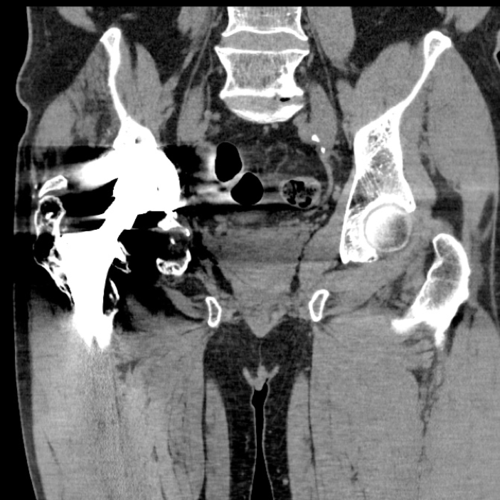

Imaging revealed anterior and medial wall deficiencies with a raised centre of rotation. The posterior column remains intact.

The pre-operative cross sectional imaging demonstrates the extent of the intrapelvic migration